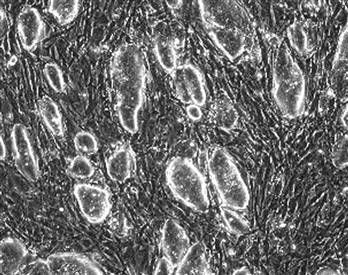

自然生長(zhǎng)的老鼠胚胎干細(xì)胞。

經(jīng)過(guò)科學(xué)家的改造,老鼠的纖維原細(xì)胞具有了胚胎干細(xì)胞的相同特征和功能。